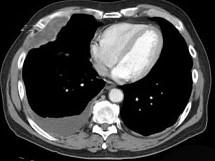

问题 70岁,男,以前是管道安装工,有石棉接触史,也有很长的吸烟史,请结合CT检查选出最可能的诊断 ( )

选项 A.胸膜肥厚 B.胸膜间皮瘤 C.石棉肺 D.神经鞘瘤 E.淋巴瘤

答案 B